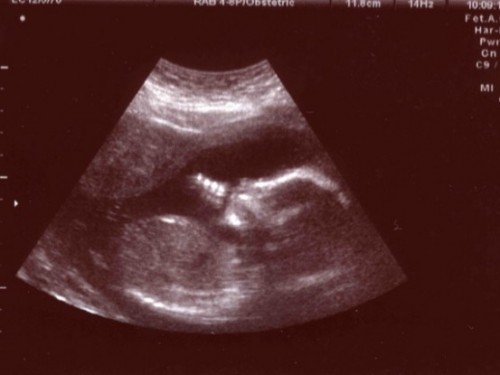

Pese a que el código penal es restrictivo en cuanto al aborto, el aborto terapéutico fue permitido por el código de salud entre los años 1931 hasta el año 1989, durante ese período si una mujer estaba embarazada y la situación ponía en peligro la vida de la mujer, la mujer que estaba en esta causalidad podía practicarse un aborto siempre que contara con la aprobación de dos médicos.

En el año 1989, ya en las últimas semanas en que Pinochet se encontraba al mando del país, se elimino la excepción del aborto terapéutico. La posición de los legisladores fue que “a la luz de los avances de la medicina hoy en día, el aborto terapéutico no esta justificado bajo ninguna circunstancia”.